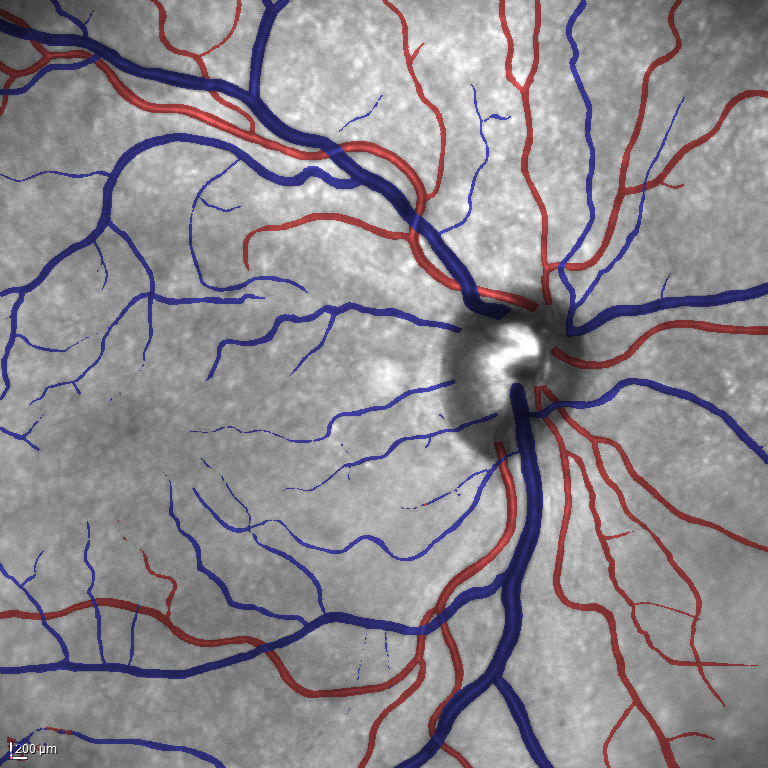

(a) Reference (b) Output (c) Width Map

From the segmentation predicted by the SegRAVIR network, our model measures the diameter of the arteries and veins. To this end, the segmentation probability map is first thresholded, using a constant value of 0.5, to obtain the medial curves of the vessels by iteratively identifying and removing border pixels while maintaining vessel connectivity, in an approach similar to the thinning algorithm presented by Zhang et al. [49]. Then, the distance transform of the medial curve mask is multiplied with the segmentation mask in a pixel-wise manner. The result is the diameter distance map with respect to the medial curves of the segmented vessels.

VI-B Vessel Width Estimation

Table VI presents a quantitative comparison of the measured diameters using the segmentation outputs of SegRAVIR and competing approaches. Using the pixel-wise annotated masks, the reference average diameter of the arteries and veins in the test set of the RAVIR dataset were measured as and , respectively. According to our analysis, SegRAVIR can accurately measure the diameter of the vessels and it achieves the smallest MAPE among the competing approaches. Specifically, in comparison to CE-Net, Iter-Net, and DU-Net, respectively, SegRAVIR is on average , and more accurate in terms of MAPE for the measured diameter of arteries and , and in terms of MAPE for the measured diameter of veins. Fig. 6 presents qualitative comparisons of reference and SegRAVIR estimated diameter maps.